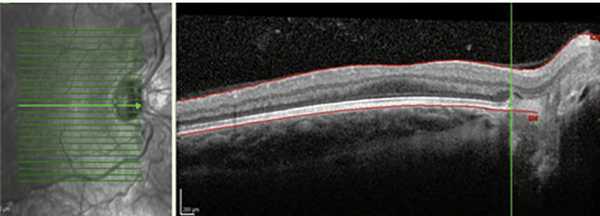

При анализе клинического состояния глаз у глубоко недоношенных пациентов выявлены некоторые особенности. На 10 (18,5%) из 54 глаз с благоприятными исходами РН, на которых в активной фазе РН локализовалась в I или II зоне, наблюдались смещение ретинальных сосудов и тракция сетчатки в носовую сторону. Данный факт свидетельствует о более ранней манифестации заболевания в назальном отделе сетчатки, что характерно для детей, рожденных на ранних сроках гестации (рис. 2) [4, 9].

Рис. 2. Смещение ретинальных сосудов и эктопия макулы в носовую сторону (данные ОКТ).